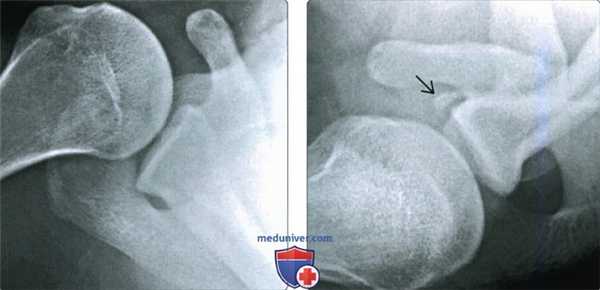

(Слева) Аксиллярная рентгенограмма, пациенте ранее вправленным вывихом, но который в настоящее время жалуется на постоянную боль; в аксиллярной проекции определяется слабое просветление по переднему краю суставной впадины.

(Справа) На рентгенограмме West Point у этого же пациента визуализируется костный отломок, прилежащий к передненижнему краю суставной впадины, перелом Банкарта. Проекцию West Point, нацеленную на передне-нижний край суставной впадины, можно использовать при КТ для визуализации небольших переломов Банкарта, которые не легко увидеть на передне-задней или аксиллярной рентгенограммах.